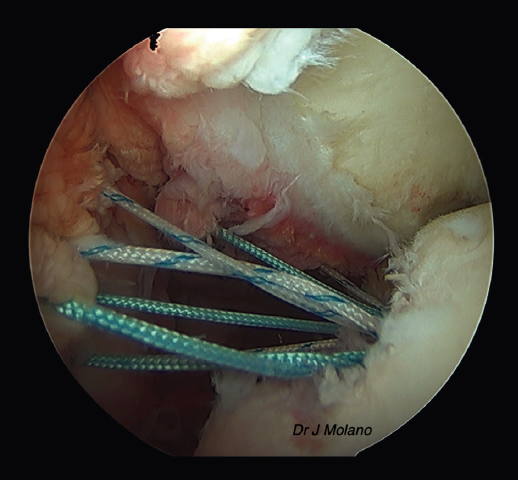

Figura 7. Visión artroscópica desde el portal superior tras anudado de remplissage, implantación intraarticular de la ligamentoplastia y reparación capsulolabral que oculta el ligamento.

Una vez realizada la reparación de Bankart, se cambia nuevamente el artroscopio al portal anterosuperior y desde el posterior vamos recuperando los 2 cabos de cada sutura a nivel del Hill-Sachs para anudarlos, en el espacio subacromial, de inferior a superior (habitualmente 4 suturas), consiguiendo el relleno del defecto de Hill-Sachs.

Tras ello, se pasa al tiempo abierto de la cirugía. Se realiza un miniabordaje axilar subpectoral de 3-4 cm, abrimos la fascia axilar y, entre el pectoral mayor y el coracobíceps, recuperamos la ligamentoplastia sintética. Una vez recuperada, se localiza el punto de anclaje en la metáfisis proximal del húmero, entre el subescapular y el pectoral mayor, medial a la corredera bicipital a nivel de la arteria circunfleja anterior. En dicha localización se realiza un brocado con una broca de 7 mm y, posteriormente, se fija con un tornillo interferencial SwiveLock® de tenodesis Peek® (Arthrex, Naples, FL, USA) de 7 mm. Este anclaje se realiza idealmente con el hombro a 90° de abducción y 90° de rotación externa (en algunos casos con lesiones óseas “límites” se realiza con menor arco de abducción-rotación externa, asumiendo una cierta limitación del balance articular) (Figuras 4 a 7).